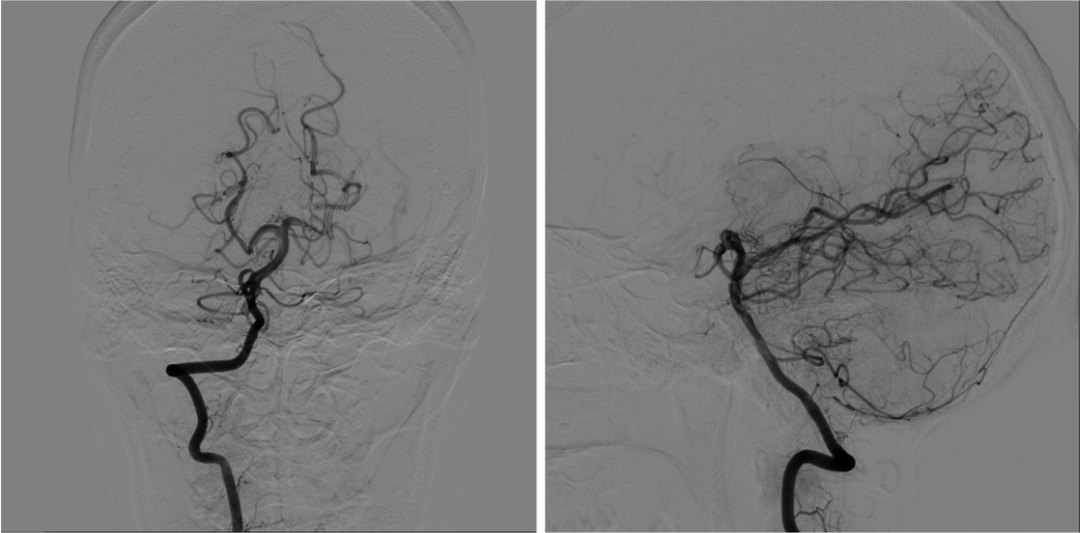

颈总动脉造影

右侧颈内动脉超选造影

左侧颈内动脉超选造影

右侧椎动脉超选造影

左侧椎动脉超选造影